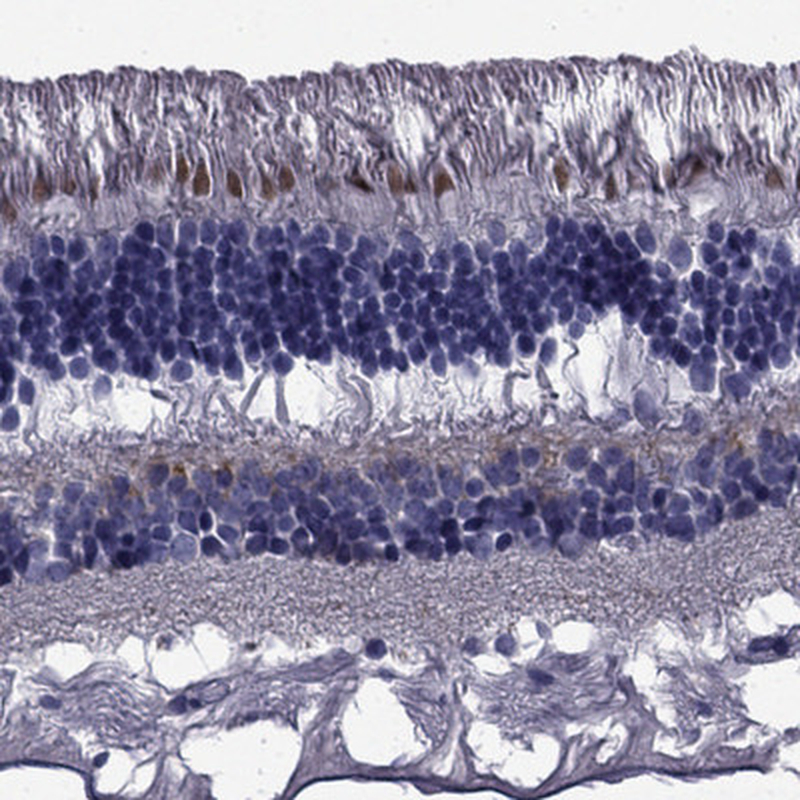

Immunohistochemical staining of human retina shows strong cytopalsmic positivity in cones.